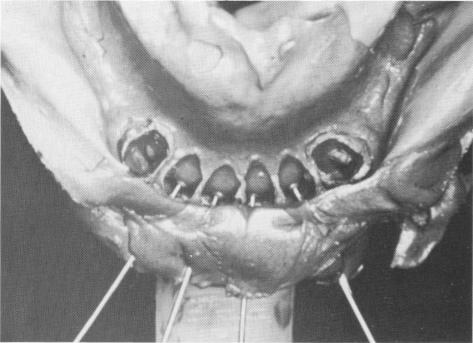

Fig. 11-88. The pins are reinserted in the rubber impression after the impression is removed from the mouth.

3 Pins reinserted in rubber impression after it is removed from mouth